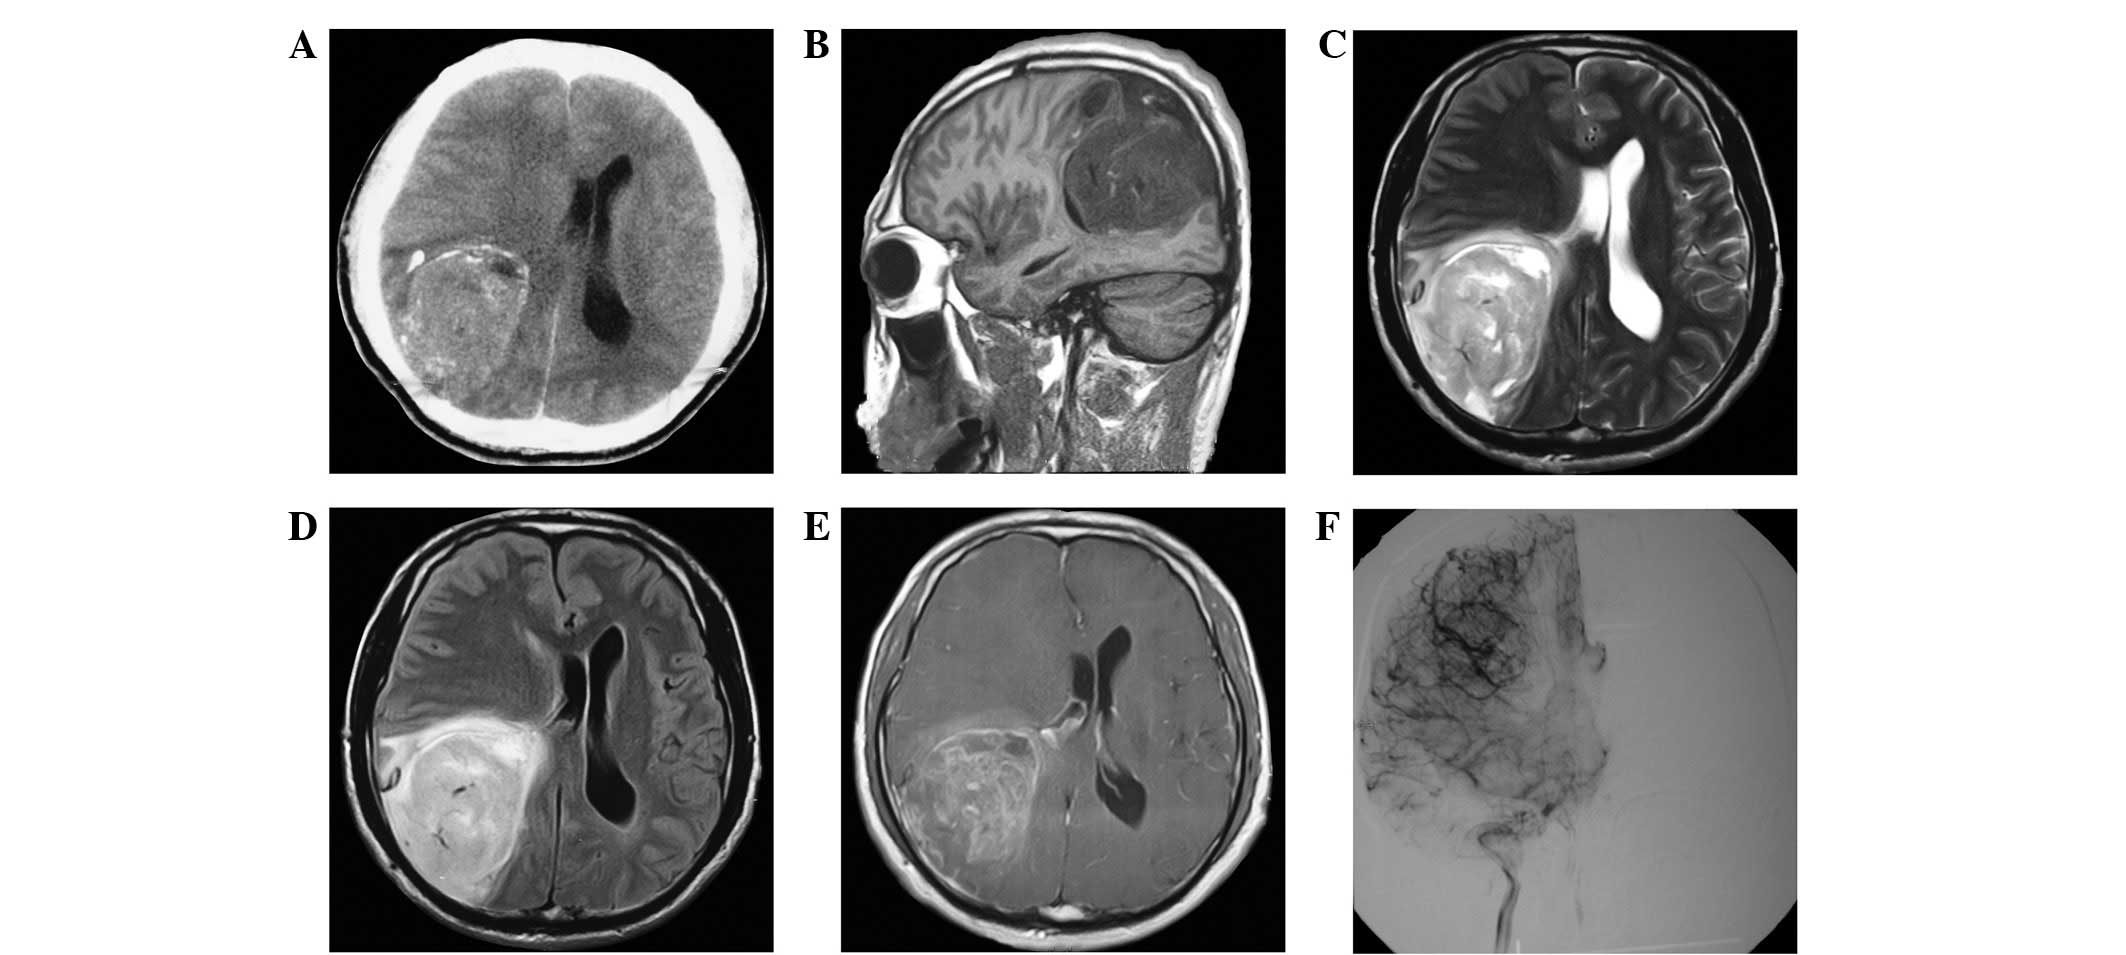

A 34-year-old man who suffered from headache and right upper-extremity weakness for 2 months was referred to The Second Affiliated Hospital of Dalian Medical University (Dalian, China) for medical care. Informed consent was obtained from the patients family. The patient exhibited no impairment of consciousness, hearing, vision or sensory perception. Physical examinations revealed that the patient exhibited decreased hearing in his left ear, upper-extremity numbness and muscle strength decline. Axial computed tomography (CT) examination of the brain showed a large, high-density mass with calcification in the right parietal-temporal-occipital area, and the top of the mass pressed against the parieto-occipital subdural matter (Fig. 1A). An MRI scan revealed a mushroom-shaped mass, which was divided by the Sylvian fissure. The mass exhibited heterogeneous hypointensity under T1-weighted imaging (T1WI) and hyperintensity under T2WI and fluid-attenuated inversion recovery imaging, which was caused by brain parenchyma deformation, with obvious peritumoral edema (Fig. 1B–D). The mass was heterogeneously enhanced following the intravenous administration of gadolinium, with prominent feeding arteries. In addition, the boundary of the tumor was enhanced, which appeared as blurriness under T2WI (Fig. 1E). The frontal view of the internal carotid artery, obtained using digital subtraction angiography (DSA), did not show an obvious mass with large arteriovenous shunts or a vascular nidus resembling a true arteriovenous malformation (AVM); however, the right middle cerebral artery and the draining vein were thickened. Based on the presurgical evaluation, it was suggested that the patient had a WHO grade II or III meningioma or AVM, as the radiological manifestations were unclear. Due to the patient's impaired function and the results of the radiological examination, a surgical resection was performed. During surgery, the partial dura mater was pushed outward by the tumor with high tension. Notably, soft, gray-red, cystic, highly liquid tissue with high-transmittance, with a jelly-like appearance, was expelled instead of adhering to the dura mater when cut radially. As expected, the insidious tumor growth boundaries were clear on the surrounding normal brain, which was covered by slightly yellowish particles on the membrane; however, the results of the pathological examination of the frozen section revealed an anaplastic glioma. The residual tumor, which was gelatinous and pinkish-gray in color, was subsequently separated in order to achieve subtotal excision. The immunostaining results (Fig. 2) were positive for glial fibrillary acidic protein (Fig. 2B); cluster of differentiation (CD) 34, which indicated the presence of blood vessel proliferation (Fig. 2C); and oligo-2, which is closely associated with oligodendrogliomas (Fig. 2F), but negative for NeuN (Fig. 2E). The Ki-67 index was 10%, which indicated a high risk of recurrence (Fig. 2D). Accordingly, the postsurgical assessment confirmed that the mass was an anaplastic oligodendroglioma (WHO III), and the postoperative treatment proceeded with adjuvant radiation and chemotherapy. Radiographic follow-up evaluation after 6 months revealed no indications of tumor recurrence.

Oligodendrogliomas are closely associated with AVMs, both in terms of histopathology and radiology (13). In a previous study, a patient was diagnosed with AVM and received embolization, yet developed a glioma 10 years later at the same site. Certain lesions appear to be oligodendrogliomas rich in vessels during preoperative diagnosis, but are subsequently pathologically confirmed as AVM through immunohistochemistry (14,15). Vascular endothelial growth factor (VEGF) receptor, Ki-67 and CD34 have been associated with abnormal tumor angiogenesis, and the overexpression of VEGF, angiogenesis (contrast enhancement or endothelial hyperplasia) and absence of seizures are considered high-risk factors for poor prognosis (13). In the present study, the thick vascular enhancement on MRI was verified as a vein using DSA; this vein was before the normal venous drainage on the hemisphere surface from the sagittal view. Furthermore, the diameter was ~2-fold that of the normal venous drainage (Fig. 1D and F). Therefore, it may be useful to conduct DSA for cases in which MRI is unable to differentiate between oligodendroglioma and AVM.